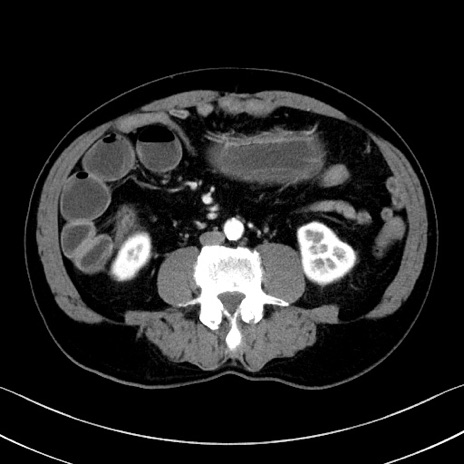

症例35(横断像)

【症例】70歳代 男性

【主訴】腹部膨満、嘔吐

【現病歴】昨日より腹部膨満感出現。本日増悪し、仙痛出現。嘔吐あり、受診。

【既往歴】糖尿病、胆摘後

【身体所見】BP 149/80mmHg、HR 74/min、BT 35.9℃、腹部:膨満、軟、圧痛なし。腸雑音減弱あり。上腹部正中切開瘢痕あり。

【データ】WBC 13500、CRP 1.72